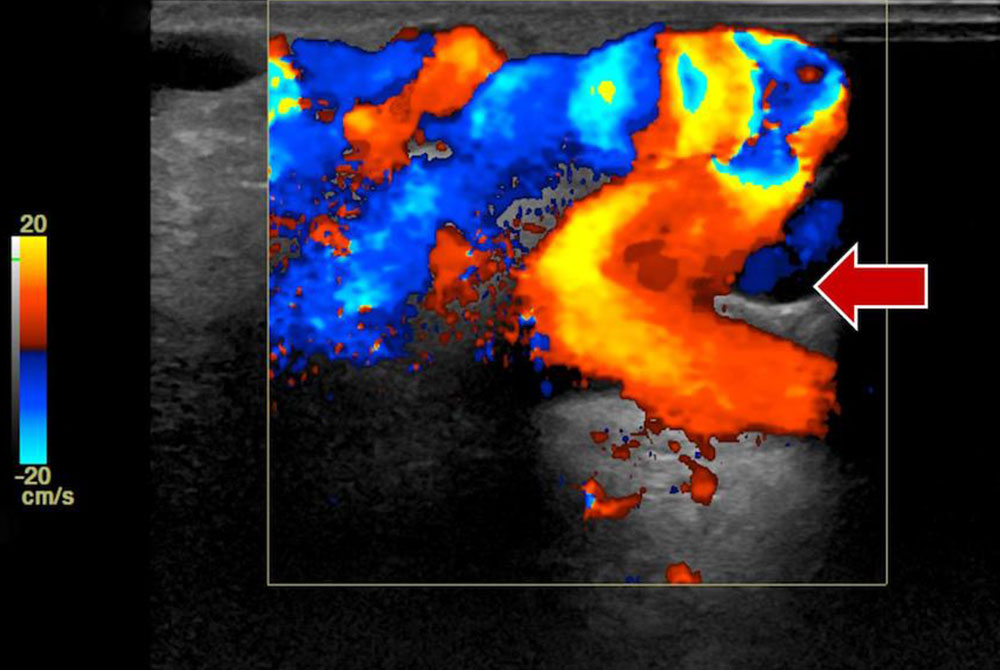

• Arteriovenous malformation: The main characteristic of peripheral arteriovenous malformation (AVM) is hyperperfusion, which can be easily detected on color-coded duplex sonography. A Doppler examination of the afferent arteries often does not show the usual triphasic resistance pattern in the affected limb, but an increased diastolic forward flow. The venous outflow also shows a significant increase in flow on the affected side. The typical respiratory variability of the venous blood flow is lacking; the high flow rate results in a continuous forward flow in draining veins. Inflowing and outflowing vessels often have a significantly larger diameter compared to the unaffected side. A supplementary examination of cardiac function by echocardiography is recommended for patients with large fast-flow vascular malformations (see special chapter on Cardiac complications).